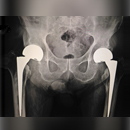

Из-за интенсивного участия в действиях, требующих использования рук, таких как вождение автомобиля, занятия спортом, сухожилие постепенно начинает разрываться. Слезы ротаторной манжеты проблематичны, поскольку они вызывают сильную боль, ощущение потрескивания, слабость или онемение в руке. Чтобы увидеть разрыв ротаторной манжеты, врач может использовать МРТ (магнитно-резонансная томография). Внимательно изучив ваше дело, врач может предложить вам сделать операцию по восстановлению манжеты ротатора.